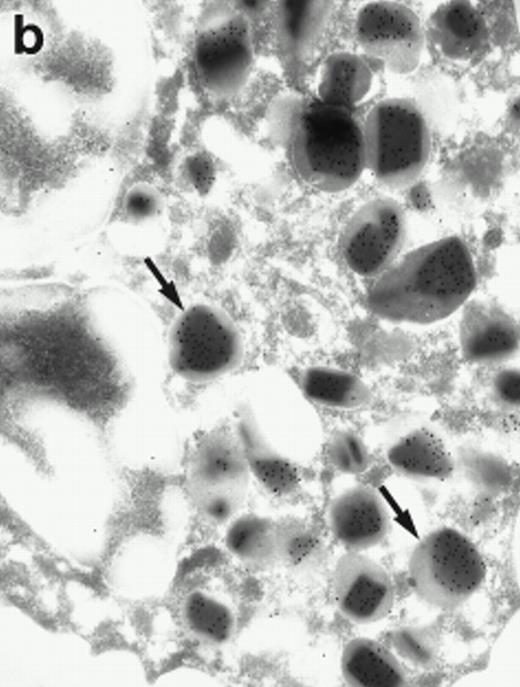

Morphologic analyses of both mature eosinophils and day-24 IL-5–induced UCC by immunoelectron microscopy were performed with proMBP-specific monoclonal antibody (J163-15E10) and with polyclonal antibody to MBP (rabbit #14). No proMBP staining was observed in peripheral blood eosinophils (Fig 6a); in contrast, MBP was localized specifically to the granule crystalline core (Fig 6b). Day-24 IL-5–induced UCC showed marked proMBP labeling of large uncondensed granules and minimal labeling of small condensed granules (Fig 6c); remarkably, proMBP was often seen as a ring around what appeared to be a granule in the process of condensing (black arrow). MBP labeling was confined primarily to condensing granules (Fig6d). Figure 7 shows results from double immunogold labeling of both proMBP (small gold) and MBP (large gold). ProMBP was concentrated in large uncondensed granules, and MBP was concentrated in condensed granules. Some granules (black arrow in Fig7b) contained labeling for MBP (primarily in the center) and proMBP (at the periphery). Controls using either normal mouse immunoglobulin or normal rabbit immunoglobulin as the primary label were negative (results not shown).

Localization of proMBP and MBP by immunoelectron microscopy. (a) A peripheral blood eosinophil labeled with anti-proMBP J163-15E10. Note the absence of specific labeling. (b) A peripheral blood eosinophil labeled with rabbit anti-MBP. Note that MBP is specifically localized to the granule crystalline core (black arrows). (c) Day-24 IL-5–induced UCC labeled with anti-proMBP. The black arrow shows localization of proMBP predominantly to the periphery of a condensing granule; very little proMBP is present in the interior of that granule. The white arrow points to a condensed granule, which lacks proMBP label. Also, note the presence of a large uncondensed granule densely labeled with proMBP proximal to the nucleus (open white arrowhead). (d) Day-24 IL-5–induced UCC labeled with anti-MBP. MBP is localized primarily to the interior of condensing granules (black arrows). (a, c, and d) Original magnification ×11,000; (b) ×15,000.